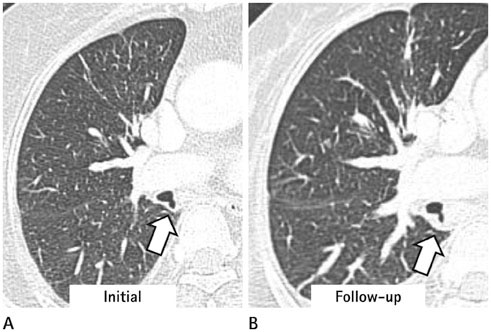

We identified two main types of ACB: blind-end (51.7%) and lobule (48.3%). The blind-end ACB was further classified into three subtypes: blunt (70%), pointy (23.3%) and saccular (6.7%). The lobule ACB was also further classified into three subtypes: complete (46.4%), incomplete (28.6%) and rudimentary (25%). Division location to the upper half bronchus intermedius (79.3%) and medial direction (60.3%) were the most common in all patients. The difference in division direction was statistically significant between the blind-end and lobule types (p = 0.019). Peribronchial soft tissue was found in five cases. One calcification case was identified in the lobule type. During follow-up, ACB had disappeared in two cases of the blind-end type and in one case of the rudimentary subtype.

The proposed classification of ACB based on imaging, and the follow-up CT, helped us to understand the various imaging features of ACB.